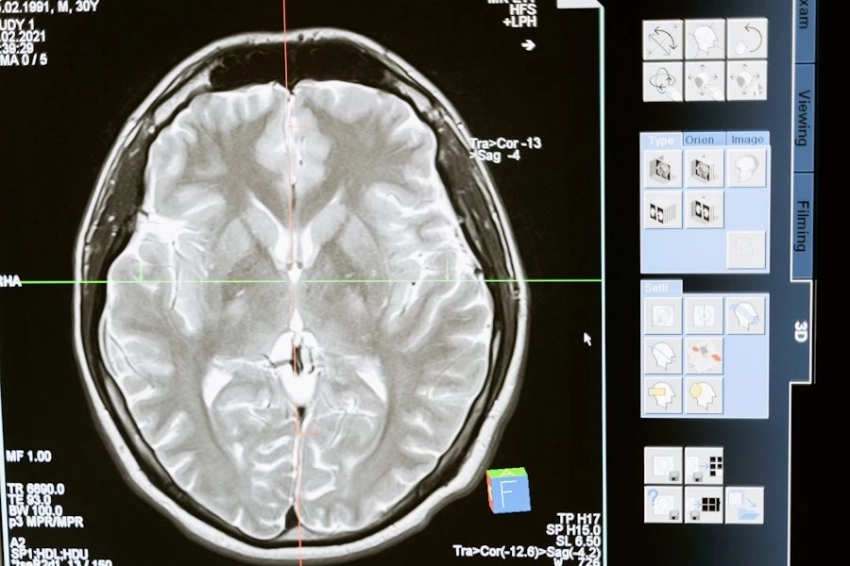

Одно из самых обсуждаемых открытий последних лет принадлежит канадским исследователям. Во время электроэнцефалографии у 87-летнего пациента, умершего прямо во время процедуры, ученые зафиксировали, что мозг продолжал проявлять активность еще в течение 30 секунд после остановки сердца. Более того, эта активность напоминала мозговые волны, характерные для сна или глубокой медитации.

Этот феномен породил гипотезу о так называемом «эффекте киноленты» — когда перед глазами человека проносится вся его жизнь, как череда воспоминаний. Возможно, в последние мгновения сознание воспроизводит самые важные, эмоционально насыщенные моменты.

Однако есть и другое, более прагматичное объяснение: мозг, переживающий кислородное голодание, искажает восприятие времени и реальности. Осколки памяти, хаотично всплывая, создают иллюзию «прожитой жизни заново».

Еще один важный аспект — гипоксия, то есть нехватка кислорода, которая наступает практически сразу после остановки сердца. Именно это состояние, по мнению ученых, может вызывать характерные для околосмертного опыта галлюцинации: свет в конце тоннеля, парение над телом, встречи с умершими родственниками.

Многие люди, побывавшие в состоянии клинической смерти, описывают свои переживания схожим образом. Исследователи считают, что в данном случае речь идет не о мистике, а о реакции мозга на экстремальные условия. Однако и это пока только гипотеза — прямых доказательств нет, сообщает echonedeli.ru.

Наблюдения канадских врачей и другие исследования предполагают, что мозг может сохранять активность даже после остановки сердца. Ученые пока не знают точно, что это — остаточная энергия, защитный механизм или нечто большее. Некоторые исследователи считают, что так называемая «последняя вспышка» может быть не просто биологическим откликом, а феноменом, требующим глубокого осмысления.